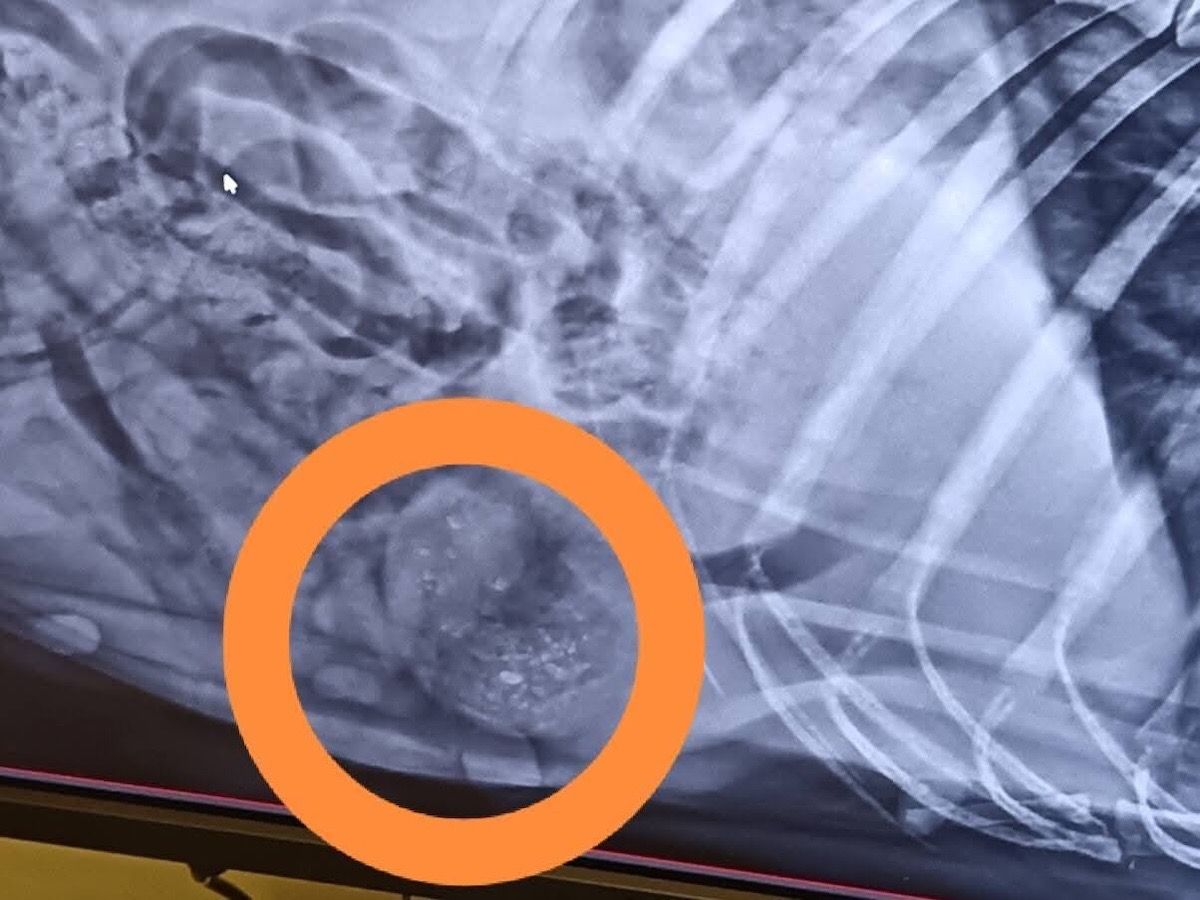

Anett hat uns heute über den aktuellen Gesundheitszustand von Mama Katica berichtet – leider mit überwiegend schlechten Nachrichten. Katica hat einen großen Weichteilbruch auf der linken Seite. Ihre Gesäugeleisten sind von kleinen Tumoren übersät.

In ihrem Bauch befinden sich Luftgewehrgeschosse.

Es wurden ein Bauchultraschall, Röntgenaufnahmen und Blutuntersuchungen durchgeführt – zum Glück waren alle Testergebnisse negativ. Der Ultraschall ergab zudem, dass sie kürzlich geworfen hat – ihre Gebärmutter ist noch offen.

Trotz all dieser Verletzungen ist Katica unglaublich tapfer. Ihr Alter wird auf etwa 13 Jahre geschätzt. Sie bekommt Schmerzmittel sowie entzündungshemmende Medikamente.

Morgen wird versucht, einen Termin in der Tierklinik in Mohács zu bekommen, um ihre Wirbelsäule orthopädisch untersuchen zu lassen.

Die heutige Tierarztrechnung konnte leider nicht bezahlt werden – und es stehen noch viele weitere Untersuchungen und Behandlungen bevor.